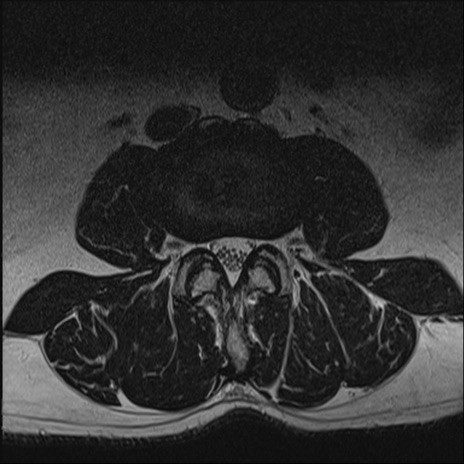

【整形】TIPS症例2 腰椎MRI T2WI(横断像)

【症例】70歳代男性

【主訴】左下肢痛

【現病歴】2週間前くらいから腰痛、左下肢痛あり。左臀部から大腿、下腿外側のしびれが常時ある。歩行とともに同部位の痛みあり。

【身体所見】Lasegue70-/60+、Bragard-/±、PTR ±/±、ATR -/-、IP 5/5、TA 5/4、TS 5/5、EHL 右第1足趾なし/3、FHL 5/5、hypersthesia(-)、足背動脈触知良好

異常所見と診断は?